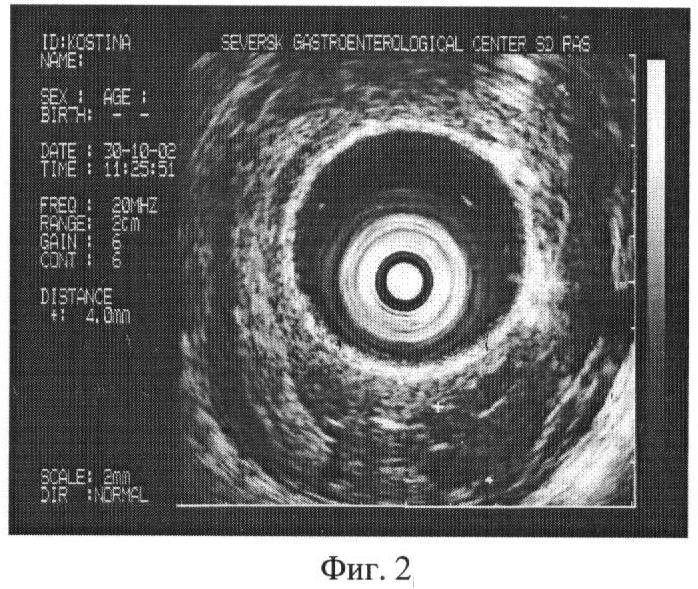

Через 2 года кровотечение рецидивировало. Больная поступила в клинику. При обследовании определено расширение вен пищевода I степени – до 2,6 мм в диаметре (фиг.1).

Проведено исследование согласно предлагаемому способу. В желудке выявлены варикозные изменения венозных сосудов. Верифицирована одна из вен, явившаяся источником рецидивного кровотечения, – 4 мм в диаметре (фиг.2). Таким образом, расширение вен желудка диаметром 4 мм свидетельствует о наличии риска кровотечения.